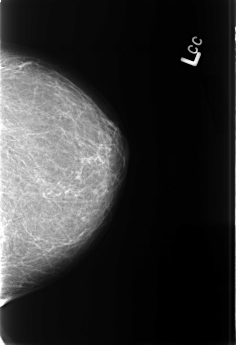

B_3394_1.LEFT_CC

LEFT_CC LINES 4480 PIXELS_PER_LINE 3056 BITS_PER_PIXEL 12 RESOLUTION 50 NON_OVERLAY